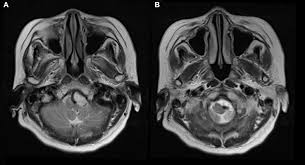

Magnetic resonance imaging has largely surpassed angiography as the imaging study of choice. Reference - ASAACCFAHA guideline on the management of patients with extracranial carotid and vertebral artery disease mnh 21471149 p aph 59955487 p a9h 59955487 p byh 59955487 p beh 59955487 p bmh 59955487 p cxh 59955487 p mdc 21471149 p Vasc Med.

Reference - ASAACCFAHA guideline on the management of patients with extracranial carotid and vertebral artery disease mnh 21471149 p aph 59955487 p a9h 59955487 p byh 59955487 p beh 59955487 p bmh 59955487 p cxh 59955487 p mdc 21471149 p Vasc Med. However data on the treatment of posterior circulation stroke are less clear. SUMMARY Ten patients with angiographically verified occlusion of the basilar or vertebral artery have been followed for an average of 275 years. Occlusion of the Vertebral or Basilar Artery Follow Up Analysis of Some Patients with Benign Outcome Louis R. Variable restenosis rates have been reported in the literature with small improvements demonstrated using drug eluting stents. Endovascular treatment of vertebral artery stenosis VAS is a safe and effective technique for treating symptoms caused by posterior circulation ischemia with high technical and clinical success rates low complication rates and durable long-term results. Clinicians must carefully balance the risks of surgery versus the limitations of endoluminal intervention before proceeding.